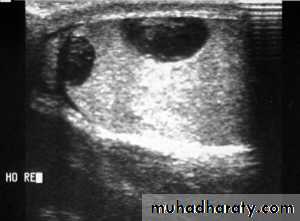

Contusion and rupture of the testis are associated with a collection of blood around the testis and cannot usually be distinguished with certainty without exploration.

O/E: scrotal swelling, bruises, Loss of testicular contour

U/S is the investigation of choice

Haematocele ( collection of blood between two layers of tunica vaginalis) should be drained and the tunica albuginea repaired after evacuation of haematoma.